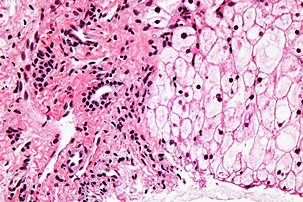

황달이 생기는 이유는 담즙색소라고 알려진 빌리루빈이 과도하게 생기기 때문입니다. 빌리루빈은 우리 몸의 오래된 적혈구가 파괴되면서 생기는 물질인데요. 이 물질은 담즙에 녹아서 우리 몸의 배설물과 함께 배출이 되는 것이 정상적이지만 빌리루빈의 과잉생산이나, 간의 장애, 간세포나 담도의 손상에 의해 빌리루빈이 역류할 경우 발생된다고 합니다.

자몽에는 간을 보호하는 물질이 함유되어 있습니다. 이는 항산화물질로 간 섬유증 발병을 감소시킨다고 보고 있습니다. 자몽은 염증과 싸우면서 간 건강을 유지하는데 좋은 과일입니다.